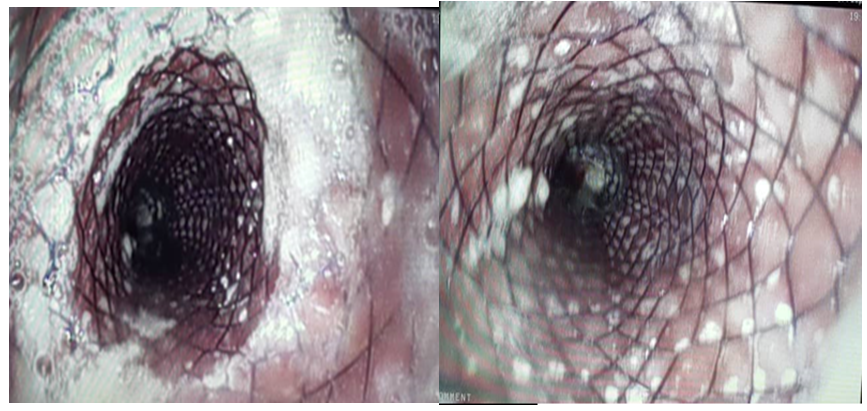

The following day, he was hemodynamically stable and off vasopressors, also his hemoglobin and hematocrit were 8.5g/dL and 24% respectively. Vital signs remained stable. Four days after operation, an esophageal barium study was performed and an esophago-pleural fistula was present (Figures 3 & 4). Fistula was closed using endoscopic esophageal stenting (Figure 5).20,21 Oral diet was started without any complications. He was discharged three days after the endoscopy procedure with 15 days total admission time. On outpatient follow-up one month after discharge, he was symptom free. A barium esophageal study was ordered to further evaluation of the stent location, which was right and the patient felt well after one month. The patient was asymptomatic with no recurrent diverticula and hematemesis at 3 months follow-up.

Figure 5 Control esophagogram after stenting without any leakage .